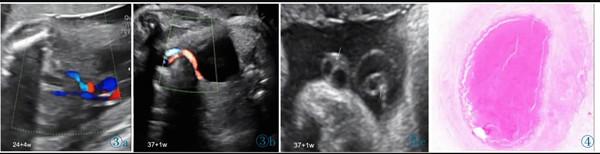

11 例中孕期超聲均可見2 條UA(膀胱水平橫切面顯示2 條UA 血流信號),超聲最后一次提示可見2 條UA 的平均孕周為(31.2±3.1)周。11 例超聲首次提示UA 數(shù)目異常(表現(xiàn)為膀胱水平橫切面UA彩色多普勒僅顯示1 條UA 及血流信號,另一側(cè)血流信號消失)的平均孕周為(36.7±2.8)周,6 例(54.4%)為膀胱左側(cè)血流信號消失,5 例(45.5%)為膀胱右側(cè)血流信號消失。7 例(63.6%)孕晚期超聲首次即提示單條UAT,這7 例臍帶游離段橫切面二維灰階圖像均顯示3 個管腔結(jié)構(gòu),其中1 條UA 內(nèi)可見稍高回聲填充且血流信號消失(圖1);1 例(9.1%)在孕34+4周提示單臍動脈,在孕37 周超聲隨訪中糾正診斷為單條UAT,因超聲提示臍帶高度螺旋,且在臍帶橫切面下見臍靜脈呈“C 形”包繞2條UA,1 條UA 內(nèi)存在血栓回聲(圖2),該病例同時合并胎兒生長受限;3 例(27.3%)整個孕期均提示單臍動脈,回顧其既往中孕期超聲均見2 條UA,晚孕期超聲發(fā)現(xiàn)1 條UA 內(nèi)存在血栓回聲(圖3)。

圖1a 臍帶橫切面。1 條臍靜脈管腔大,內(nèi)為無回聲。2 條UA 管腔小,栓塞側(cè)內(nèi)為稍高回聲(血栓回聲),通暢側(cè)內(nèi)為無回聲。圖1b 臍帶橫切面。臍靜脈及通暢側(cè)UA 內(nèi)見方向相反的血流信號,栓塞UA內(nèi)無血流信號(箭頭所示)。圖1c 臍帶縱切面。臍靜脈內(nèi)為無回聲,栓塞UA 內(nèi)等回聲為血栓(箭頭所示)。圖1d 臍帶縱切面。臍靜脈內(nèi)可見血流信號,栓塞UA 內(nèi)無血流信號。圖1e 通暢側(cè)UA:舒張末期血流流速增加,S/D 和PI 偏低。圖1f MCA:舒張末期血流流速增加,PI 值降低。Figure 1a.Cross section of cord.No echo is shown in the lumen of umbilical vein(the larger one).Two UAs have smaller lumens,and hyperecho is found in the occluded UA(thrombus).Figure 1b.Cross section of cord.Opposite blood flows are shown in umbilical vein and the normal UA,and no blood flow signal is shown in the occluded UA(as indicated by the arrow).Figure 1c.Longitudinal section of cord.There is no echo in umbilical vein and the arrow indicates the thrombus in the occluded UA.Figure 1d.Longitudinal section of cord.There is blood flow in umbilical vein and no blood flow in the occluded UA.Figure 1e.The unobstructed UA: the end diastolic blood flow velocity increases;S/D and PI decreases.Figure 1f.MCA: the end diastolic blood flow velocity increases;PI decreases.

圖2 a 臍帶橫切面。臍靜脈呈“C 形”包繞2 條UA,1 條UA 內(nèi)存在血栓回聲(T:血栓)。圖2b~2d 臍帶高度螺旋。Figure 2 a.Cross section of umbilical cord.One clogged UA is in parallel with the other unobstructed one and both of them are surrounded by umbilical vein(T: thrombi).Figure 2b~2d.Hyper-coiling of umbilical cord.

圖3 誤診為單臍動脈病例的超聲圖像。圖3a:孕24+4 周,膀胱兩側(cè)均可見UA 血流信號;圖3b:孕37+1 周,膀胱一側(cè)UA 血流信號消失;圖3c:臍帶橫切面見臍靜脈呈“C 形”包繞2 條UA,箭頭所示其中1 條UA 管腔細(xì)小,內(nèi)為稍高回聲(血栓)填充。圖4 臍帶病理(HE 染色)。UA 內(nèi)見血栓形成,管壁彈力纖維梗死。Figure 3.Ultrasonography misdiagnosed as single umbilical artery.Figure 3a: At 24+4 weeks,the blood flow of two UAs is seen in both sides of bladder.Figure 3b: At 37+1 weeks,only one UA is seen in the level of bladder.Figure 3c: In the cross section of umbilical cord,two UAs are surrounded by umbilical vein.As indicated by the arrows,one UA has smaller lumen which is filled with a slightly higher echo(thrombi).Figure 4.The pathological finding of umbilical cord (HE stain).The UA lumen is filled with thrombi.The necrosis of elastic fibers are found in arterial wall.